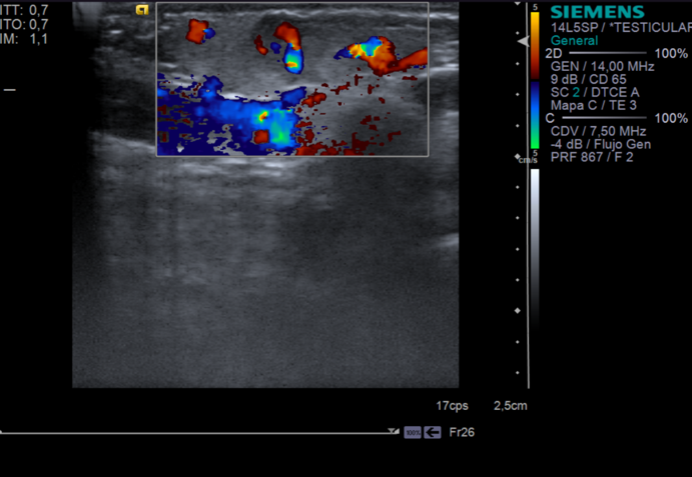

Ecografía partes blandas

Ecografía Doppler-color